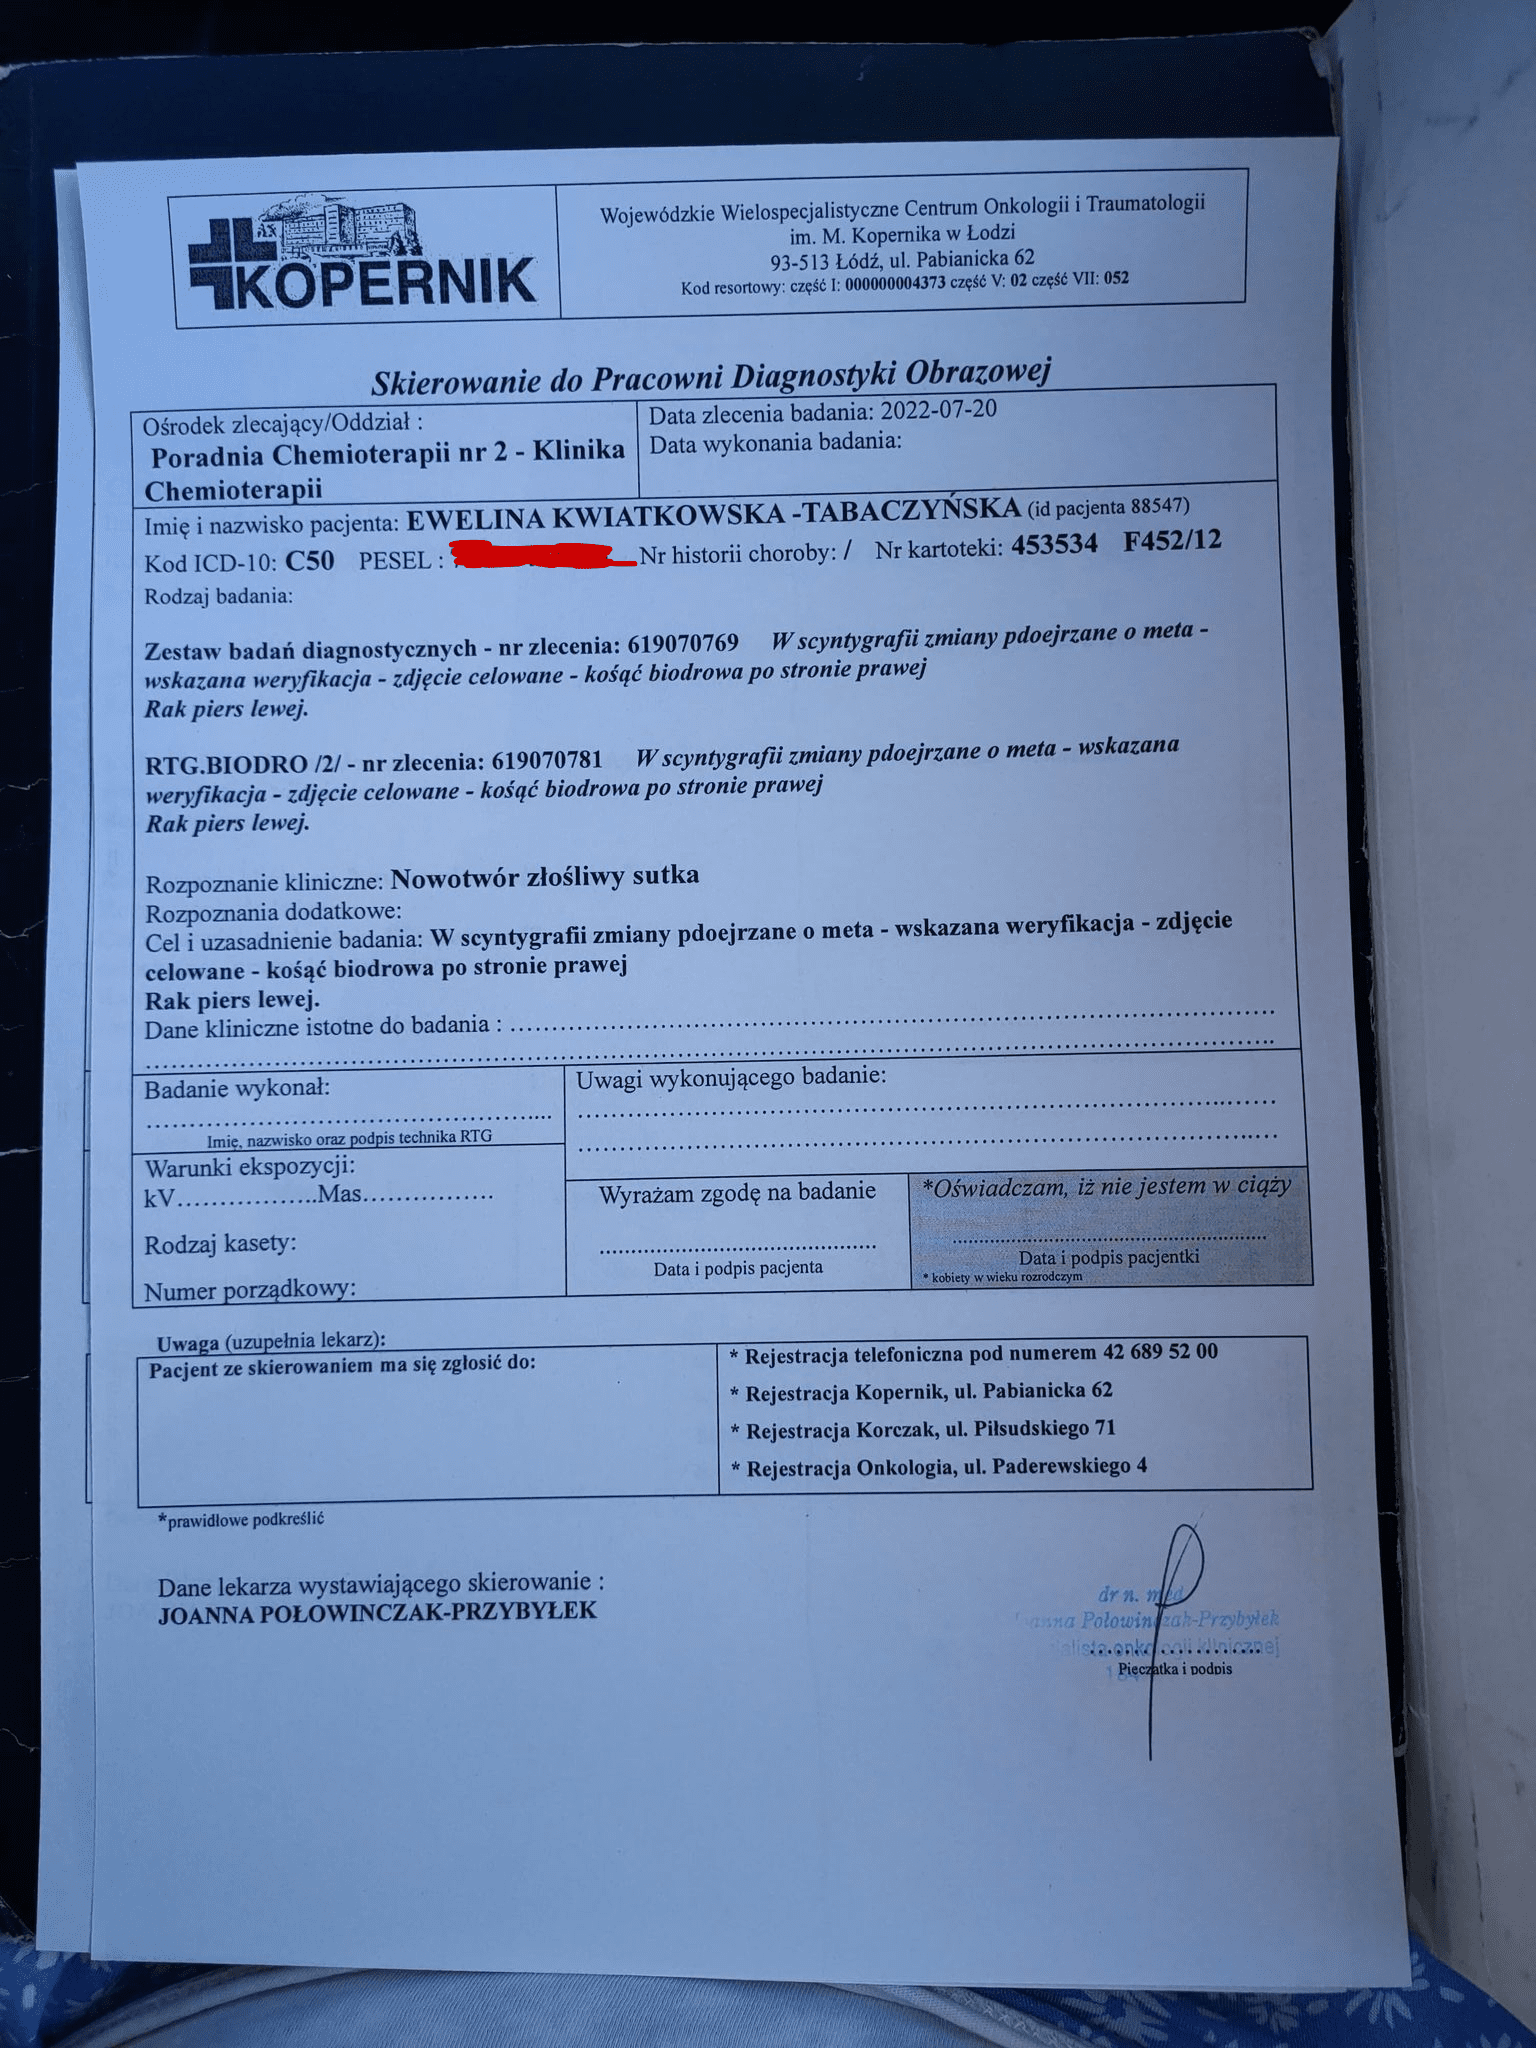

Złośliwy nowotwór piersi, po kolejnych badaniach stwierdzono przerzuty do kości.

W dalszym ciągu jestem diagnozowana, kolejne badania mają za zadanie zdecydować lekarzom podjąć odpowiednie kroki.